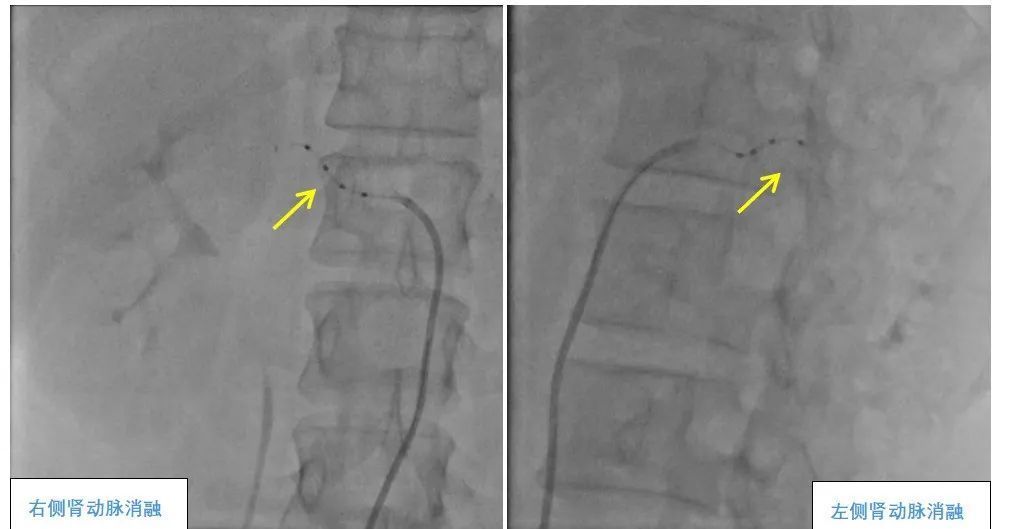

团队联合心内科、妇产科、介入导管中心、重症医学科、泌尿外科、手术麻醉中心等多个科室,反复推演手术流程,同时制定了应急预案。手术当天,在麻醉团队的严密监测下,夏文豪教授团队通过微创方式,将消融导管精准送至孔女士双侧肾动脉。术中,团队对肾动脉主干及分支进行全面评估,共定位38个消融靶点,整个手术仅用时1小时,出血量不足5毫升。

肾动脉去交感神经消融术(RDN)